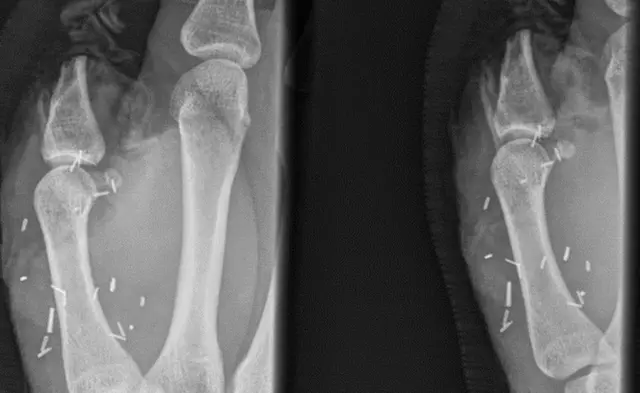

காளை தாக்கி கை கட்டை விரல் துண்டான ஆஸ்திரேலியாவைச் சேர்ந்த கால்நடை வளர்ப்பு தொழிலாளி ஒருவருக்கு அவரின் கால் கட்டை விரல் பொருத்தப்பட்டுள்ளது.

எட்டு மணி நேரம் நடைபெற்ற அறுவை சிகிச்சை மூலம் அவரின் கால் கட்டை விரல் முதலில் பிரித்தெடுக்கப்பட்டது. அதன் பின்னர் நடைபெற்ற இரண்டு அறுவை சிகிச்சைகள் மூலம் துண்டிக்கப்பட்ட கை கட்டை விரல் பகுதியில், கால் கட்டை விரலானது வெற்றிகரமாக பொருத்தப்பட்டது.

`பகுதியளவு கால் கட்டை விரலை இடம் மாற்றுவது சாதாரணமானது. ஆனால் மிட்செலுக்கு நடந்து போல, முழு கால் கட்டை விரலையும் இடம் மாற்றுவது அரிதானது.` என சிட்னி கண் மருத்துவமனை தெரிவித்துள்ளது.